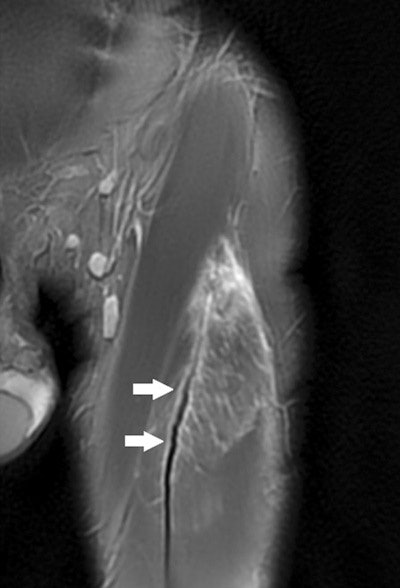

Serner, Roemer, and colleagues developed a detailed multidimensional MRI assessment approach for acute groin injuries that focuses on musculotendinous injuries, including location, grading, and lesion extent, as well as other nonacute findings, and determines intra- and interrater reproducibility of such assessments.

The protocol the researchers developed assessed grade, location, and extent of muscle strains; perilesional hematoma; and other nonacute findings commonly associated with groin pain, such as location and extent of edema.

Musculotendinous lesions were graded identically for acute and nonacute lesions on a scale from 0 to 3, with 0 being no imaging abnormality and 3 being complete musculotendinous disruption/tear or avulsion from the tendinous attachment.

The researchers found almost perfect intra- and interrater agreement (κ = 0.81-1.00) for lesion presence/absence, number of acute lesions per athlete, and muscle location, as well as lesion grading and edema location in the axial plane. Edema location in the coronal plane had substantial agreement (κ = 0.70-0.85).